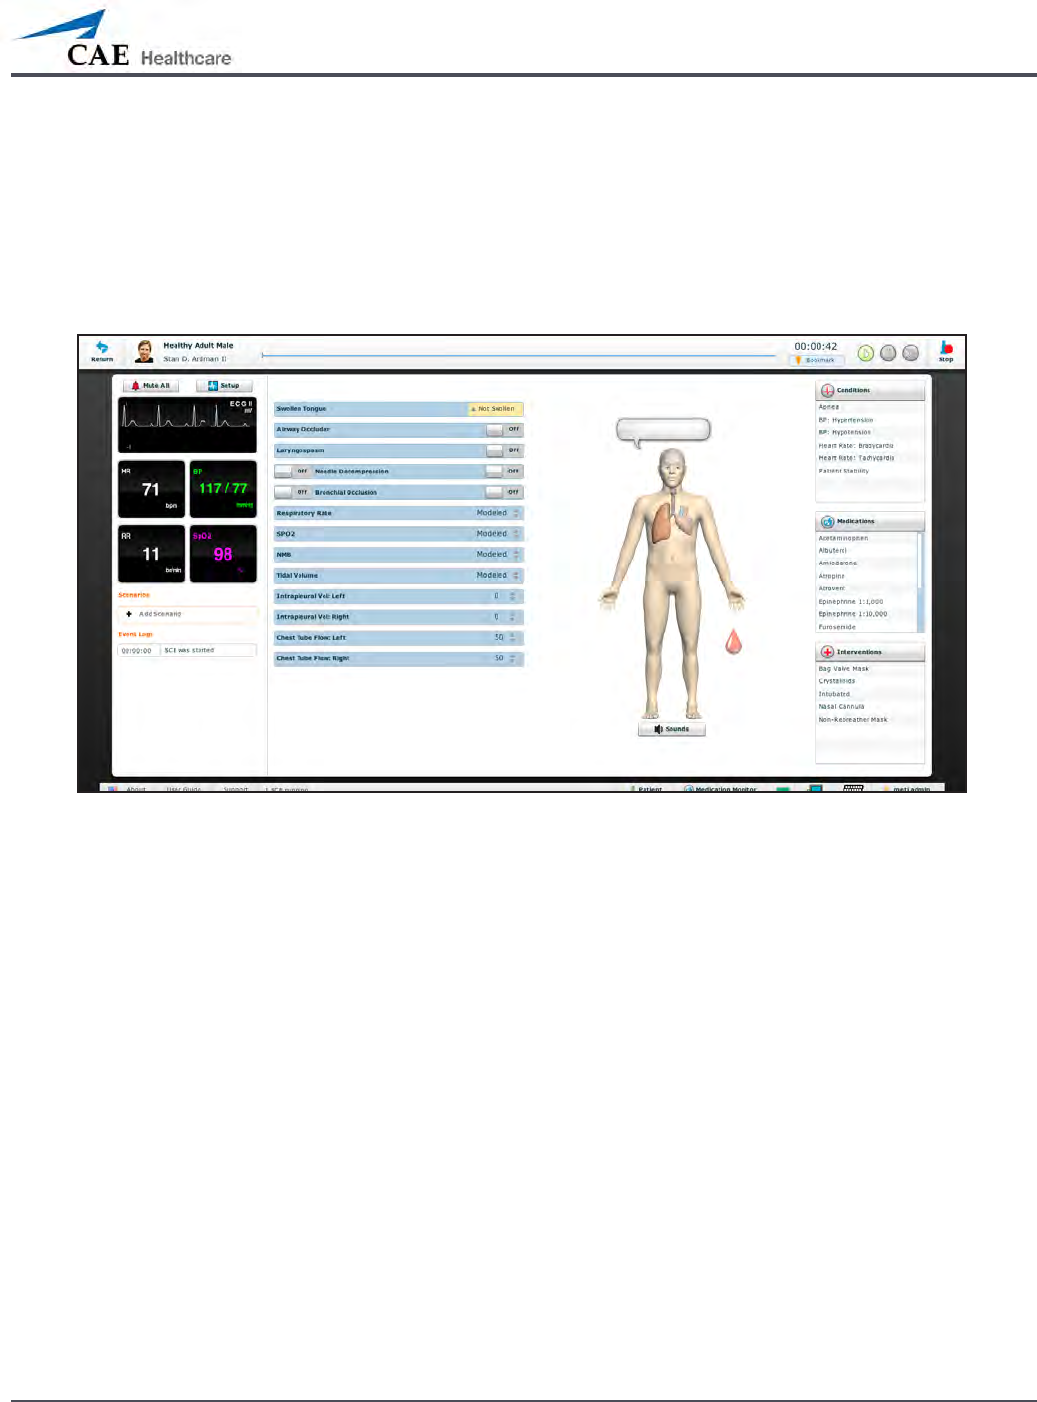

The Run Screen

126